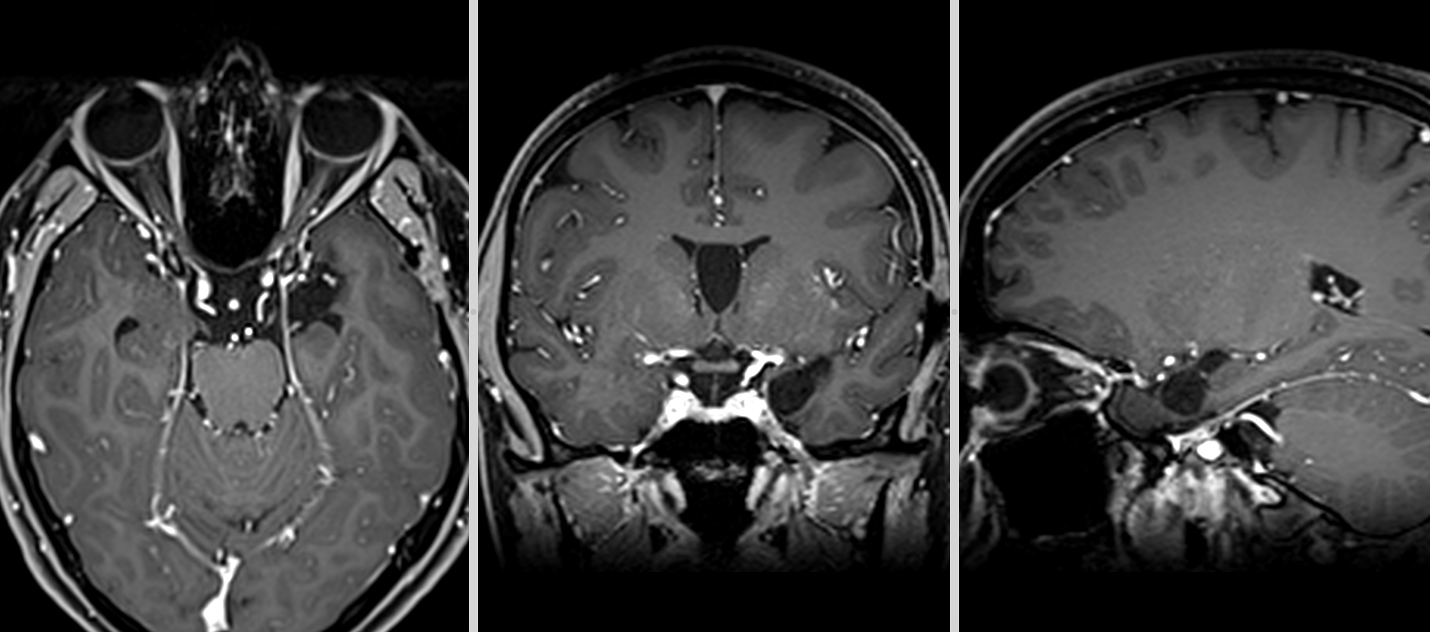

Operația s-a desfășurat în condiții foarte bune, fără incidente, iar tumora a putut fi rezecată complet, fără afectarea structurilor din jur.

Primele imagini RMN realizate imediat după intervenție au confirmat absența complicațiilor. Câteva săptămâni mai târziu, un nou control imagistic a arătat clar rezultatul: tumora fusese îndepărtată în totalitate.